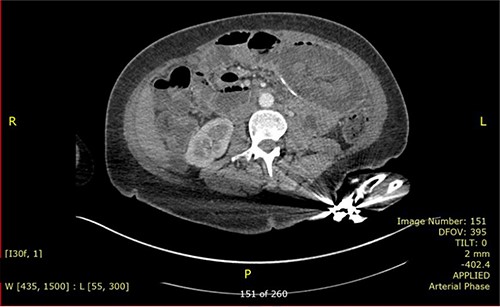

A 37-year-old lady presented with 1-day history of sudden onset of severe generalized abdominal pain that was associated with multiple episodes of vomiting. She had occasional similar episodes before, but those were usually milder and were self-resolved. Her past surgical history includes RGYBP surgery 23 years ago and six caesarean sections. She had lost 11 stones of weight in 1 year after the gastric bypass surgery. On physical examination, her abdomen was distended and diffusely tender. Her blood investigation showed low Hb (85 g/dl), raised C-reactive protein (146) and normal white cell count. She had computed tomography (CT) scan (Fig. 1) which concluded intussusception of small bowel with an area of intramural gas highly suspicious of bowel ischaemia. Diagnostic laparoscopy was decided.

CT scan is the preferred imaging modality for early identification of intussusception [9]. Characteristic findings are target signs and multiple concentric rings as seen in this case. While CT can diagnose intussusception, there is limitation in identifying its underlying aetiology. Other imaging modalities, such as plain abdominal films or ultrasonography, can be used but is less practical in diagnostic purpose compared to CT scan.